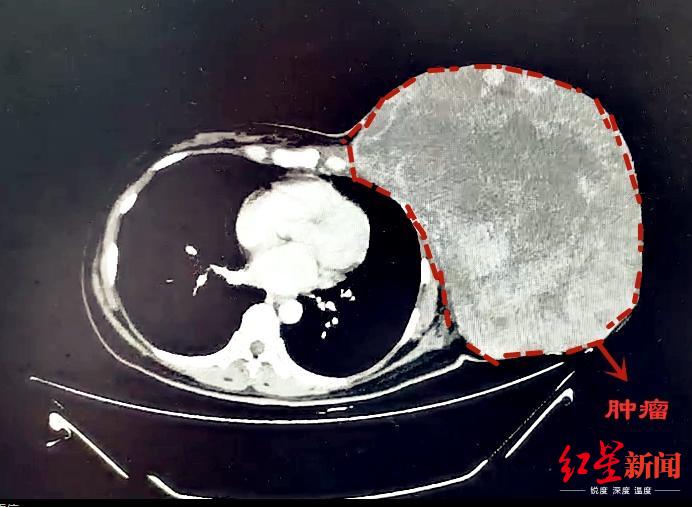

乳腺肿瘤已成为女性常见的疾病之一。然而,对于47岁的蒋女士来说,她的乳腺肿瘤只能用“心惊胆颤”来形容——直径约30cm、重达12斤!

CT影像

2年多前,蒋女士无意间发现左侧乳腺有一个包块,大约枣子般大小。因为没有疼痛等不适的感觉,她认为“可能问题并不严重”,未进行过系统化的治疗。不过,近半年来她发现包块不仅没有缩小,反而呈现出疯长的趋势。发展到现在,包块已经长到“篮球大小”,严重影响了外观,就连走路等生活日常都存在问题。

针对难点和风险,多学科小组进行了充分的准备及并制定应对措施。9月25日,经过4个半小时的手术精细剥离,将近12斤重的巨型肿瘤才被成功完整摘除。后经病理诊断,确定为交界性叶状肿瘤。经过恢复,近日蒋女士顺利出院。